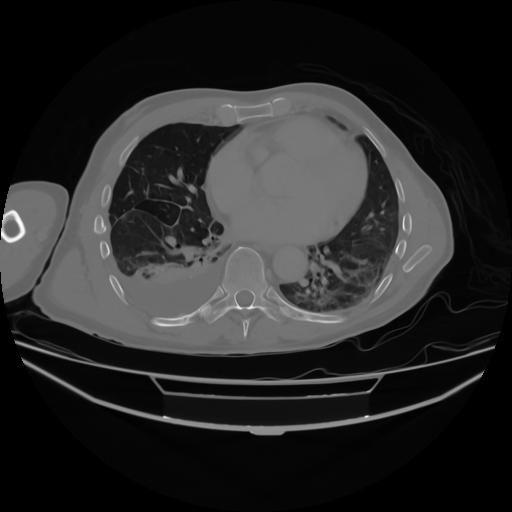

4 CUERPO,CE,Axial,3.0,CUERPO,,